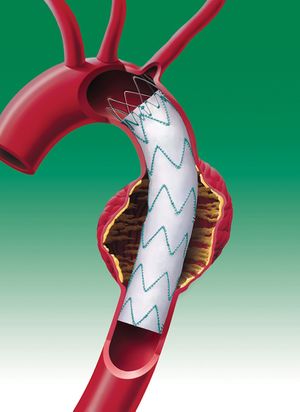

حديثا بدأ الأخصائيون بإستعمال تقنية غير جراحية لمعالجة المرضى ذوي الحالات الخطرة جداً لتمدد الأوعية الدموية الأبهري البطني. هذه التقنية مفيدة للمرضى الذين لا يمكن لم الخضوع للجراحة بسبب وضعه الصحي.

الإجراء يتضمن إستعمال قسطرة لإدخال أداة تسمى وصلة حلقة فاتحة Stent Graft. الحلقة الفاتحة توضع داخل الشريان في موقع التمدد. يجرى الدم خلال الحلقة الفاتحة، مما يؤدي إلى خفض الضغط على جدار الشريان الضعيف. هذا الإنخفاض في الضغط يمكنه أن يمنع التمدد من تفجير الشريان.

مزايا الإجراء

- لا يتضمّن أي تخدير عام

- إقامة مستشفى أقصر (حوالي 24 ساعةَ)

- تحسّن أسرع

- لا يترك ندب كبيرة.

يجب ملاحظة أن أنه لم تظهر نتائج علمية قوية تدعم هذا الإجراء لحد الأن كون الدراسات تستغرق عدة عقود من الزمن.